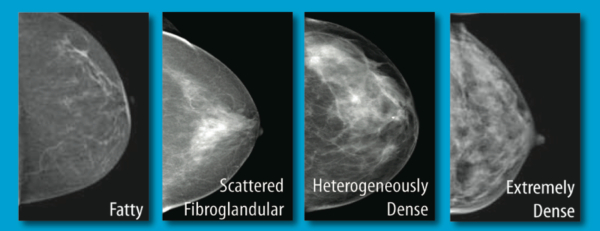

Breast Tissue Density awareness

- 49 percent were aware breast cancer detection can be affected by breast density.

- 53 percent were aware that dense breast tissue is a risk factor for breast cancer.